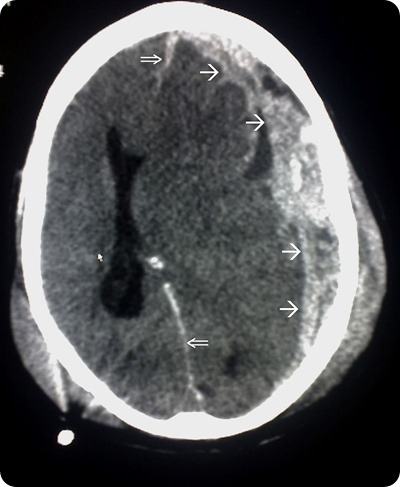

Head trauma CT scan

CT scan flowing head trauma, the single arrows mark the spread of the subdural haematoma and the double arrows mark the midline shift. Source: commons.wikimedia.org

Neuroimaging is a key technique in terms of diagnosing SBS. Intracranial pathologies such as cerebral edema and subdural and subarachnoid hemorrhage may be identified with the help of CT scans. These scans are usually the tool of choice in emergency situations.